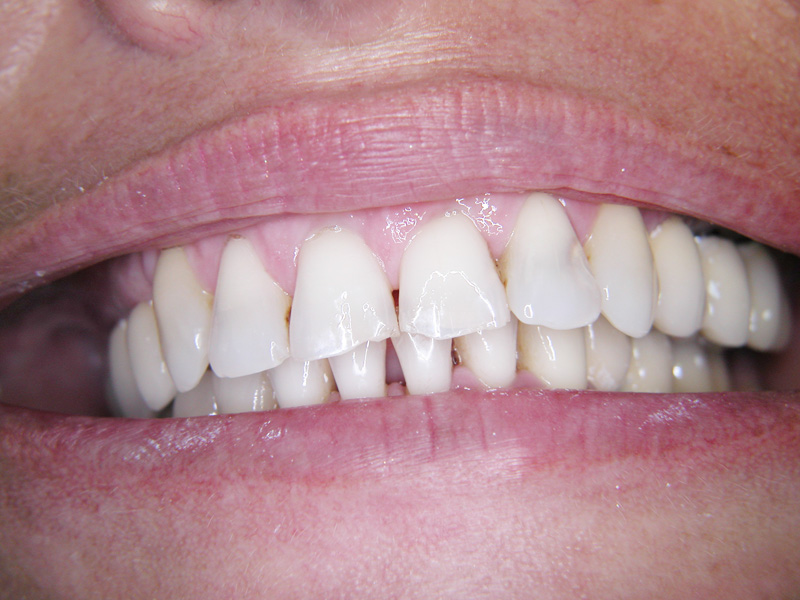

Implante - Galerie Foto

Caz I